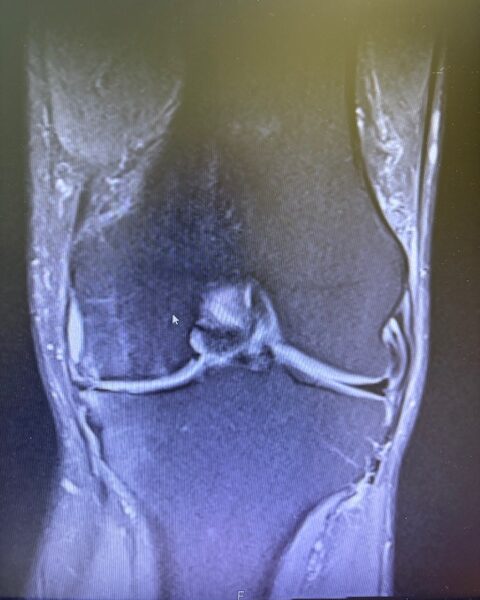

Ο ακτινολογικός έλεγχος (ακτινογραφίες/μαγνητική τομογραφία) ανέδειξε προχωρημένη οστεοαρθρίτιδα του έσω κονδύλου, με πλήρη διατήρηση του έξω διαμερίσματος και της επιγονατιδομηριαίας άρθρωσης. Με βάση αυτά τα ευρήματα, ο ασθενής ήταν ιδανικός υποψήφιος για μερική (μονοκονδυλική) αρθροπλαστική γόνατος.

Πραγματοποιήθηκε απεικόνιση και ψηφιακός σχεδιασμός της επέμβασης, ώστε να προσδιοριστεί με ακρίβεια το μέγεθος και η θέση των προθέσεων. Ο στόχος ήταν να αποκατασταθεί η φυσιολογική μηχανική του γόνατος, διατηρώντας ανέπαφα τα υγιή τμήματα της άρθρωσης, τους συνδέσμους και τους γύρω μυς.